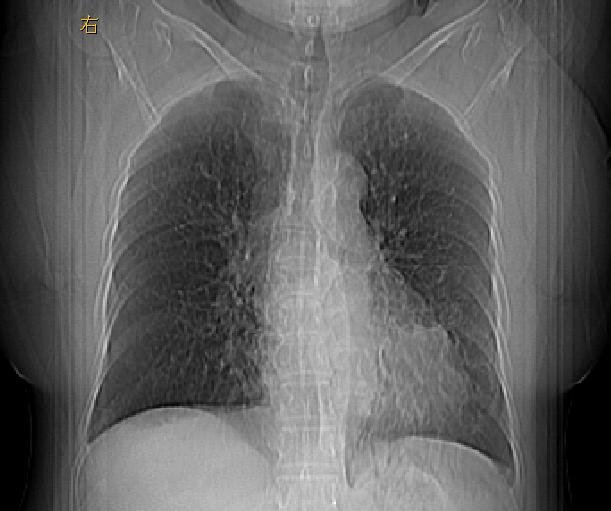

女性病人,56岁,反复咳喘30余年,伴大量脓痰,偶有痰中带血。

此病例在科室里有较大的争议,我认为是先天性肺囊肿(理由是:两者起病年龄都较轻,都有咯血及脓痰的症状,而先天性肺囊肿壁薄;而支扩的囊腔旁一般都能看到伴行的血管影,形成“印戒”征)。以上为个人的意见,请高手们指点一下。

影像符合支气管扩张伴感染,先天肺囊肿壁薄,而后天支扩因反复感染壁多较厚,有慢性支气管炎病史。最后诊断靠病理,先天肺囊肿的囊内无尘埃。

本例应为支气管扩张并感染,与囊肿区别在于其大小,分布,壁改变,与肺动脉关系,形态等来鉴别,要点大家都说得差不多了,囊肿要大些,分散些,靠外围一些,而支扩靠内一些,聚拢些,小一些且易聚拢呈葡萄状,不能单从囊壁厚度来评价,特别是有粘液栓类的改变更加支持支扩,有时支扩亦与囊肿混在一起并存.个人意见仅供参考.